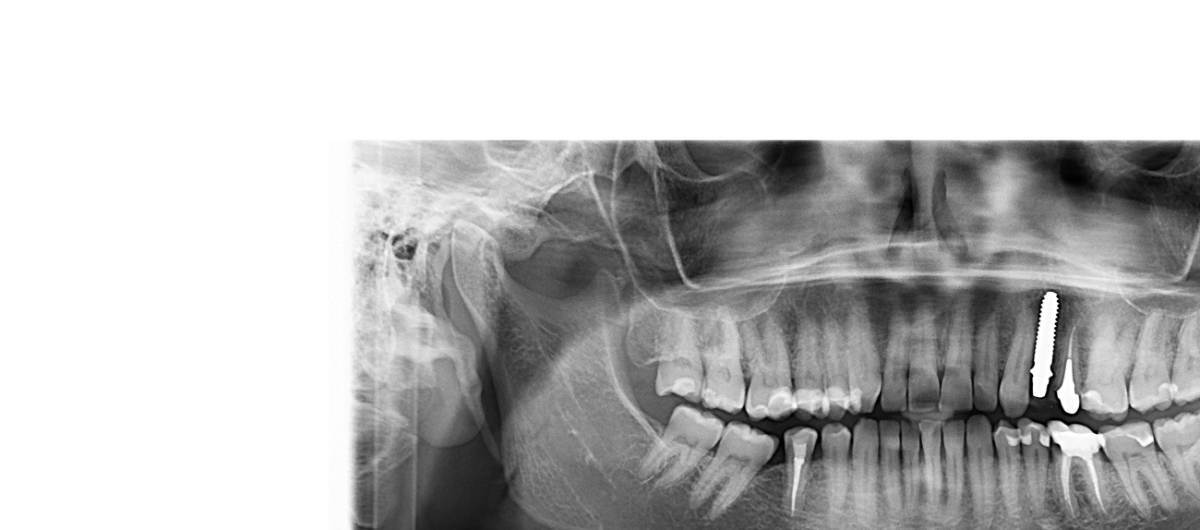

Karamel Опубликовано 7 часов назад Поделиться Опубликовано 7 часов назад (изменено) Добрый день, уважаемые стоматологи. Очень нужна консультация по поводу установки импланта. 6 февраля 2026 года была проведена одномоментная имплантация верхней левой 4-ки имплантом из диоксида циркония white SKY 3514 от bredent. На 3-й день после имплантации начались сильные боль, отдавали в нижнюю челюсть, температура 37,5. Это не смотря на прием антибиотика Панцеф с первого дня. Антибиотик принимала 10 дней, температура снизилась на 8 день. Боль прошла, оставался дискомфорт. На 11-ый день установили временную пластиковую коронку (на 5-ку с циркониевой вкладкой и на имплант). Но все время есть ощущение давления или какого-то распирания между клыком и имплантом. Хирург утверждает, что все нормально, это коронка давит. Ортопед через 14 дней снял коронку, что-то подпилил и снова надел. Но ощущения какого-то давления остались. Сделали панорамный снимок. Я не врач, но мне кажется, что имплант упирается в клык. Может его лучше выкрутить, пока не сильно поздно? И можно ли это сделать аккуратно? Очень переживаю за клык... Изменено 5 часов назад пользователем Karamel опечатка Ссылка на комментарий

Karamel Опубликовано 2 часа назад Автор Поделиться Опубликовано 2 часа назад Большое спасибо за ответ. На данный момент боли нет ( прошло чуть более месяца со дня имплантации), но есть какое-то ощущение распирания где-то в десне между имплантом и клыком Периодически возникают кратковременные ноющие ощущения (например, когда ела творожок из холодильника). Десна выглядит неплохо, так и хирург сказал, и я сама вижу. Если по снимку судить нельзя, то необходимо сделать КТ? Ссылка на комментарий